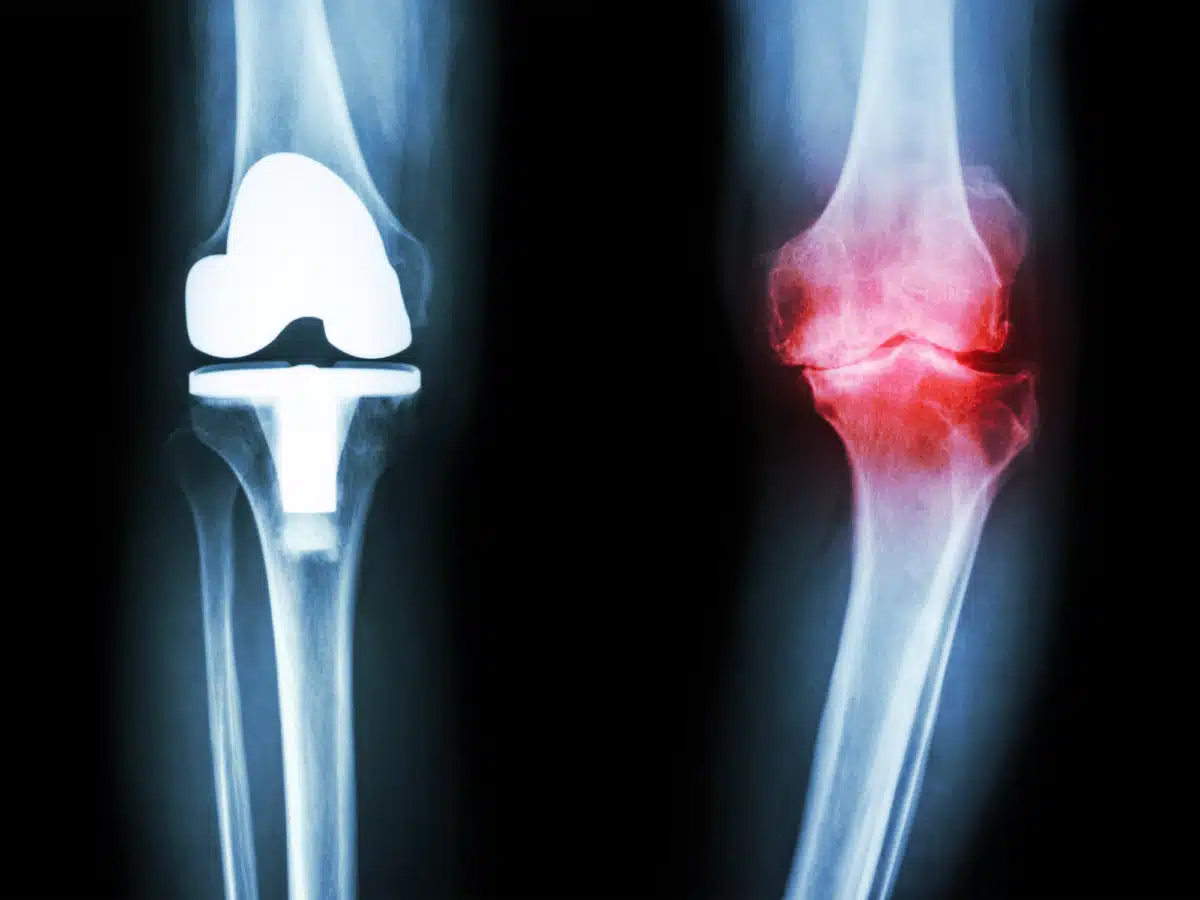

في هذه المرحلة تكون الركبة قد وصلت لحالة كبيرة من الضرر ويلجأ الأطباء في تلك المرحلة لأن يستبدل مفصل الركبة المتضرر بآخر صناعي من خلال إجراء جراحي ويحتاج الشخص بعدها إلى فترة راحة كبيرة ثم يبدأ من بعدها فترة تأهيل ليكون قادر على العودة لأنشطة حياته بشكل طبيعي.

تحدث عادة خشونة الركبة في حالة تلف غضروف المفصل وتعرضه للتآكل والتلف، وفي حالة إهمال علاج خشونة المفاصل في حالاتها الأولى قد تتدهور أوضاع المفصل بشكل كبير وصولاً للدرجة الربعة من الخشونة التي تستدعي تدخل جراحي لتغيير المفصل.

ويكون العلاج الوحيد لتلك الحالة أن يقوم المريض بإجراء عملية استبدال مفصل الركبة.

وتعد هذه المرحلة الأكثر صعوبة حيث يكون وضع الركبة غير صالح وبحاجة لإجراء عملية تغيير المفصل.

- ازدياد التآكل في الغضروف والعظام مما يتسبب في تشوه شكل المفصل بالكامل.

- تقويم للمفصل: ويكون عن طريق تغير المفصل بالكامل أو الجزء المتضرر فقط ويكون المفصل عبارة عن قطعة تحتوي على معدن أو بلاستيك تسهل على المريض استعادة المرونة أثناء الحركة كما في المفصل الطبيعي.